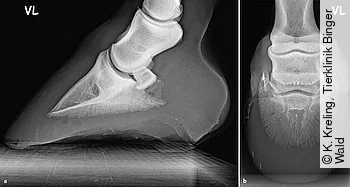

Röntgen

Manchmal kann ein Röntgenbild zusätzlich wichtige Informationen liefern, vor allem, wenn der Verdacht auf Beteiligung tieferer Strukturen oder auf eine großflächige Unterminierung besteht. Es empfiehlt sich, die Anfertigung einer seitlichen Zehen- sowie einer Oxspring-Aufnahme (Abb. 2 a und b).